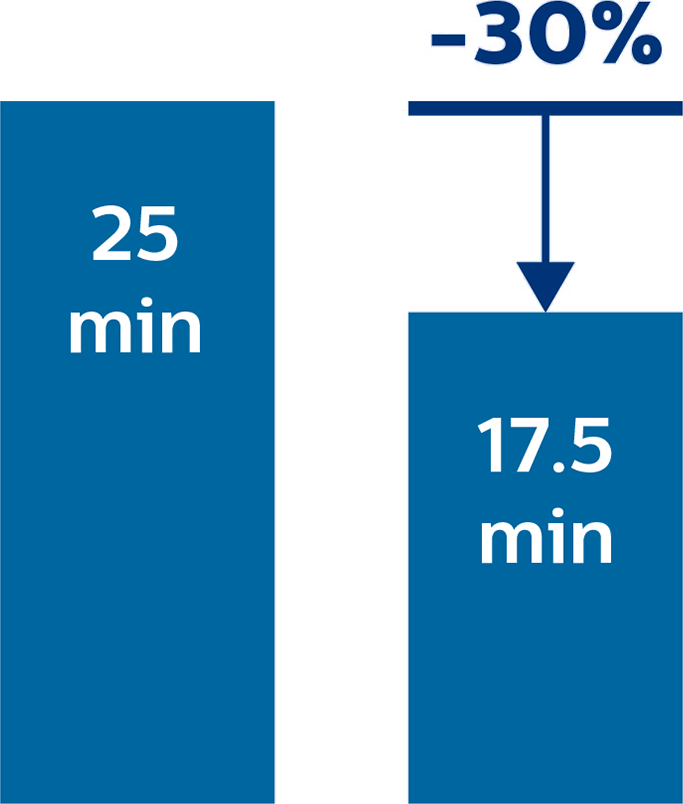

Hydrocephalus post hemorrhagic Both pictures show a ventriculoperitoneal shunt. With our previous scanner our hydrocephalus protocol needed about 25 min. With Ambition the examination time is about 14 min. including a CSF PCA sequence to show flow in the aqueduct.

Increasing the number of patients per day with Ambition

According to Dr. Junge, the department used to typically scan three or four patients per day with their previous system. However, this number instantly increased when they began using the Ambition. “Without much effort, we almost immediately doubled the number of patients to approximately six or eight per day,” says Dr. Junge. “We have only been using the system for three months and we plan to scan more patients in the future. I think our daily capacity can grow to ten or more patients per day.”